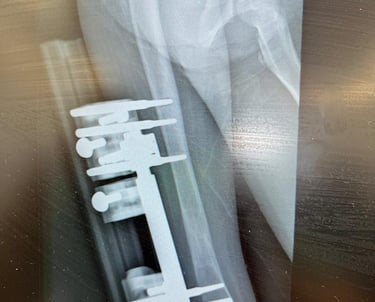

Sequelas pós-trauma ou fratura

Pseudoartrose ou falha de consolidação óssea